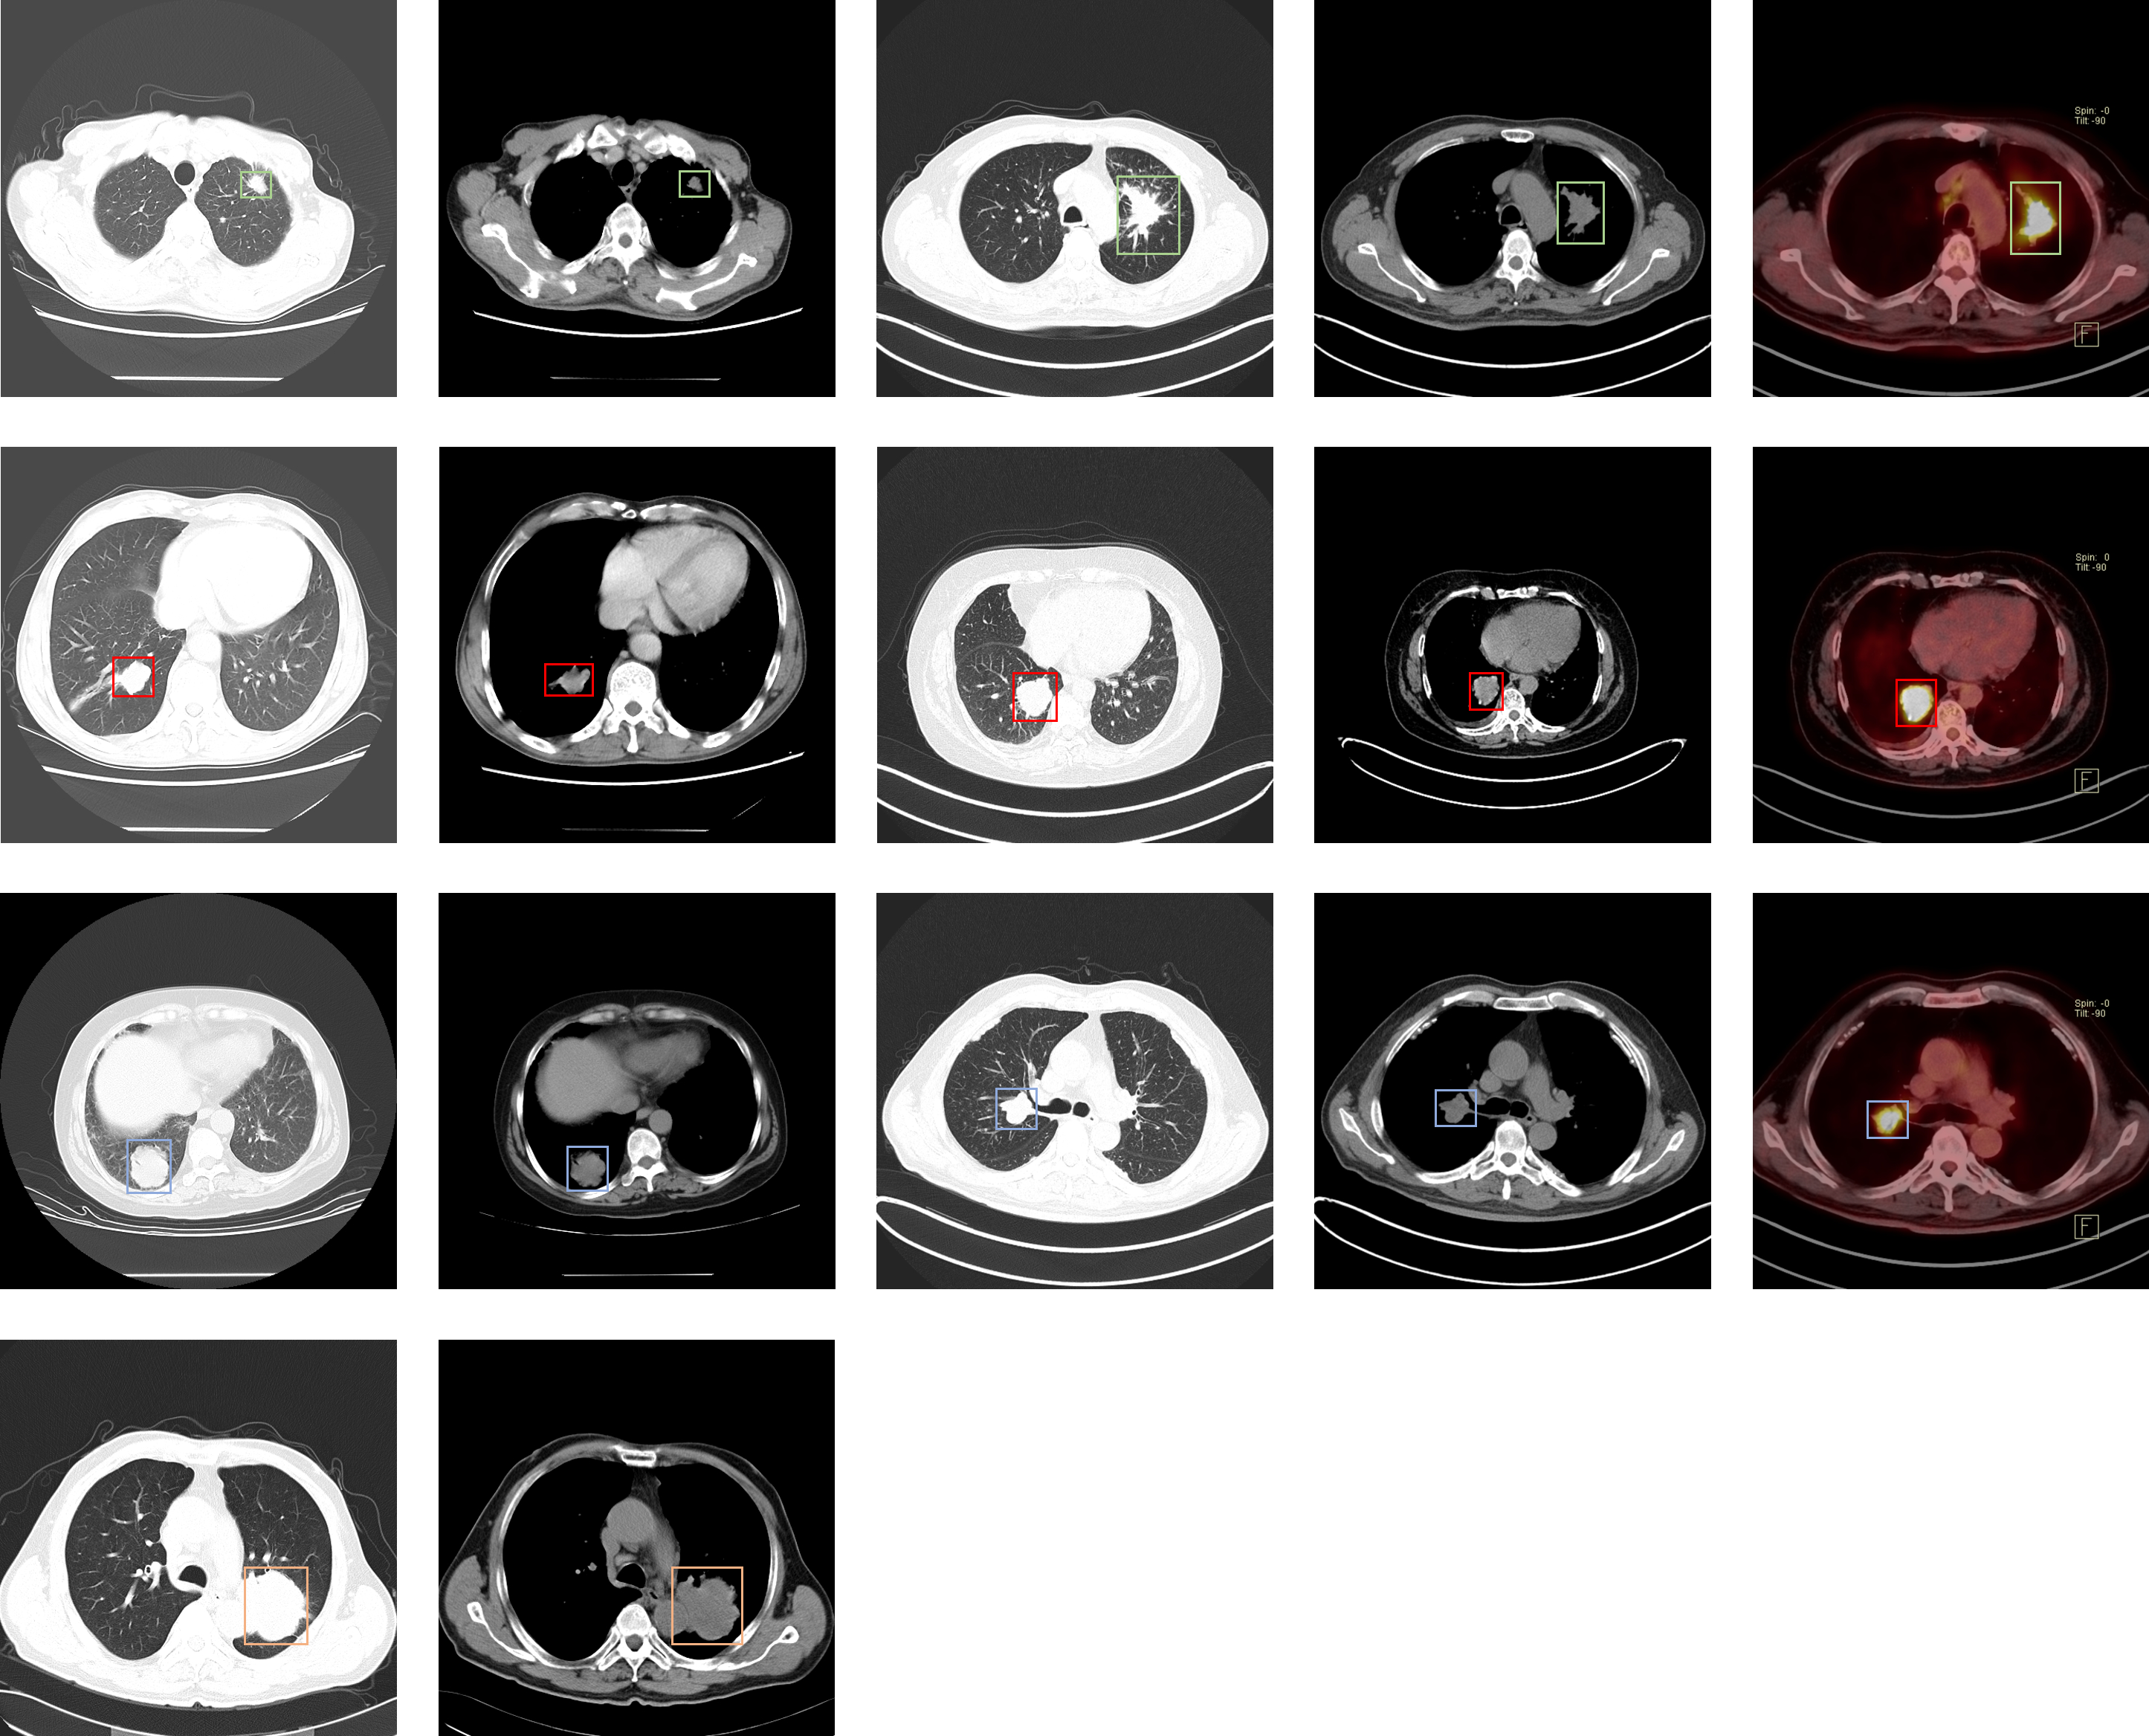

Lung-PET-CT-Dx

| 名称 | 标注内容 | 类型 | 模态 | 数量 | 标签格式 | 文件格式 |

|---|---|---|---|---|---|---|

| Lung-PET-CT-Dx | 肺癌 | 目标检测 | CT | 363 | xml | dcm |